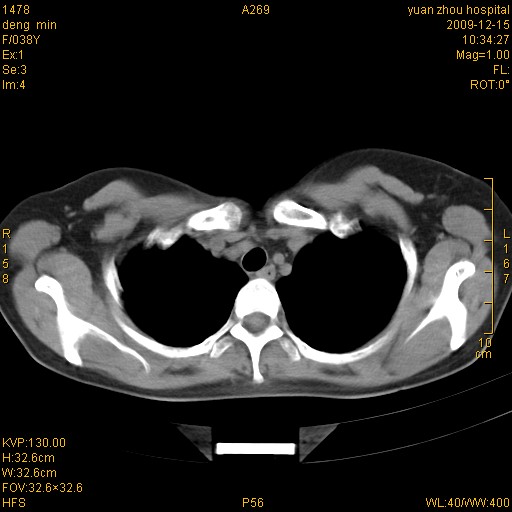

标题: CT23919:F38Y 咳嗽月余 [打印本页]

标题: CT23919:F38Y 咳嗽月余

右肺中下叶、左肺上叶舌段及左肺下叶支气管扩张合并感染。